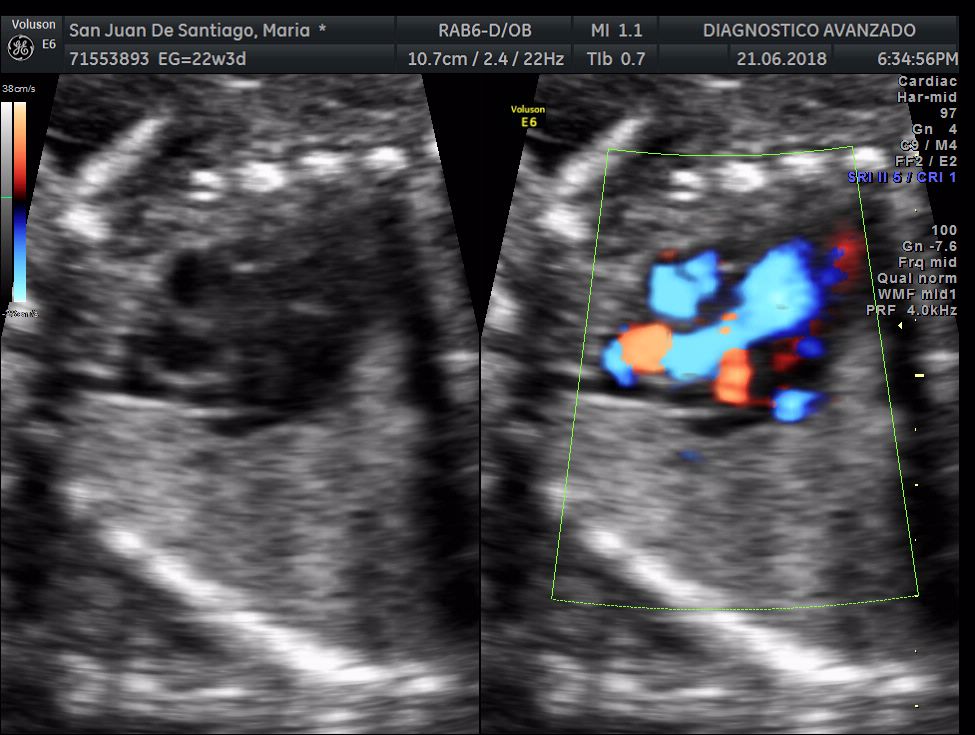

¡Hola a todos! Hoy hemos ido a hacer la tradicional ecografía 3D de la niña, os dejamos todo el material (aunque es un poco demasiado).